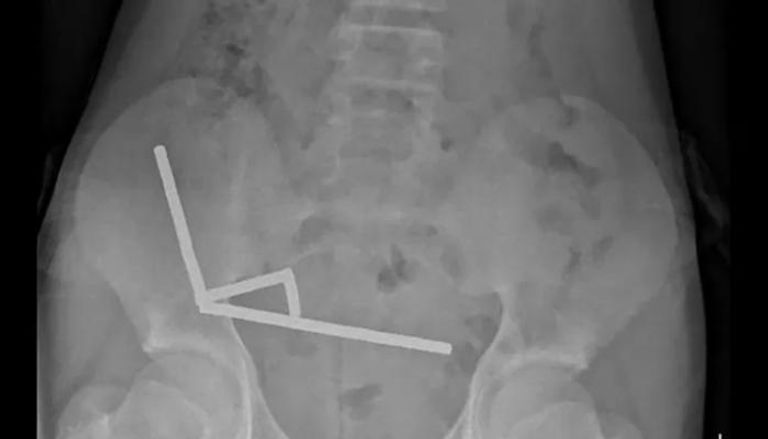

وأظهرت الأشعة أن المغناطيسات التصقت داخل الأمعاء مكوّنة أربع سلاسل متصلة، ما أدى إلى التصاق أجزاء من الأمعاء الدقيقة والغليظة وتلف في أنسجتها نتيجة الضغط المغناطيسي المستمر.